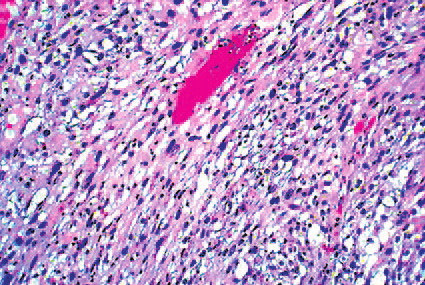

Read MoreSpindle cell scc = الكارسينوما الشائكة _مغزلية الخلايا